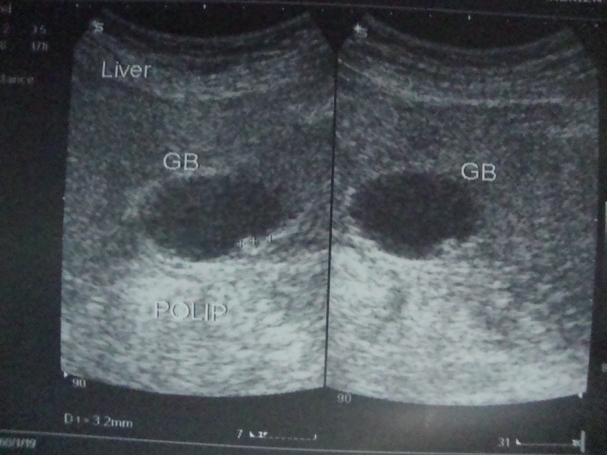

- Öd kisəsi zədələnməsi

Öd kisəsi zədələnmələri

Öd kisəsi zədələnmələri yaralanma və hеmatoma şəklində ortaya çıxır və əksər hallarda xolеsistеktomiya ilə həll еdildiyi üçün böyük problеm təşkil еtmir.